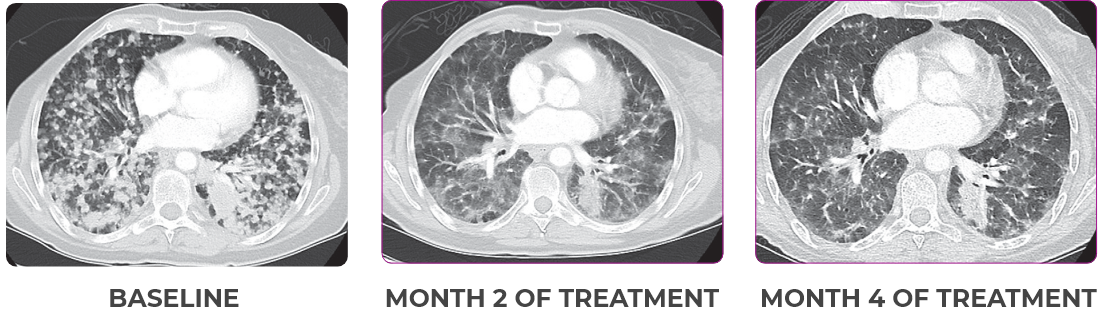

NSCLCa PATIENT WITH BRAIN

METASTASES1-3

- 76-year-old female with NSCLC that metastasized to the brain and liver

- PRa of primary lung nodules to VITRAKVI® (larotrectinib) confirmed at 2 months1

Response to VITRAKVI1,2

- Partial response to treatment that was confirmed at 2 months (34% tumor reduction)

- Patient remains on VITRAKVI after more than 4 months of treatment

Response in primary and metastatic lesions1

SCAN 2: BRAIN

MRIa imagery of the brain. Green circles indicate baseline brain metastases.1

aMRI, magnetic resonance imaging.